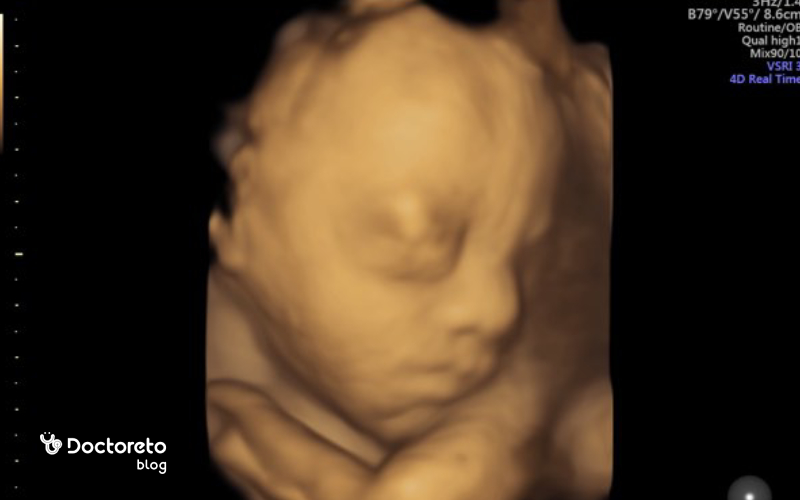

سونوگرافی در هفته ۲۸ بارداری

در هفته ۲۸ بارداری معمولاً سونوگرافی روتین انجام نمیشود و بیشتر بررسیها از طریق معاینه و آزمایش خون و ادرار صورت میگیرد. با این حال، اگر پزشک به مشکلی مانند رشد غیرطبیعی جنین، کاهش یا افزایش مایع آمنیوتیک، یا احتمال عوارض بارداری مشکوک باشد، ممکن است در همین هفته سونوگرافی تجویز شود. این سونوگرافی میتواند اطلاعات دقیقی از وضعیت جنین، حرکات، ضربان قلب و رشد او ارائه دهد.